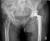

Exeter Hip

Manufactured by Stryker

Categorised under: Orthopaedics > Hip > Femoral stem - cemented

Biomechanics of Exeter hip replacement:

Modular with a choice of larger 28 and 32 mm heads

bigger head provide greater stability,but Increase volumetric wear and lead to the use of thinner layer of poly

No collar ,therefor,neck cut level & orientation are not critical

Polished – allow subsidence to stable position

Centralizer allow subsidence without excessive forces on cement

Double tapered

Stainless Steel

Designed by Ling & Lee - 1st implanted in 1970

NJR: 95% survival at 15 years